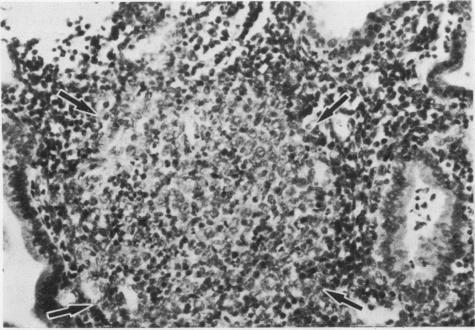

Endometrial biopsies were obtained from 32 women with suspected pelvic inflammatory disease, of whom 23 (72%) had histopathological evidence of endometritis. Chlamydia trachomatis was isolated from the endometria of nine (39%) women (chlamydia group) but not from the other 14 (non-chlamydia group). Severe plasma cell endometritis and lymphoid follicles with transformed lymphocytes were significantly more common in the chlamydia group than in the non-chlamydia group. This suggests that C trachomatis is an invasive endometrial pathogen which often causes severe inflammation. The association was independent of predisposing factors such as use of intrauterine contraceptive devices.

对32名疑似盆腔炎的女性进行了子宫内膜活检,其中23名(72%)有子宫内膜炎的组织病理学证据。从9名(39%)女性的子宫内膜中分离出沙眼衣原体(衣原体组),而在其他14名女性(非衣原体组)中未分离出。重度浆细胞性子宫内膜炎和伴有转化淋巴细胞的淋巴滤泡在衣原体组中比非衣原体组中更为常见。这表明沙眼衣原体是一种侵袭性子宫内膜病原体,常引起严重炎症。这种关联独立于诸如使用宫内节育器等易感因素。